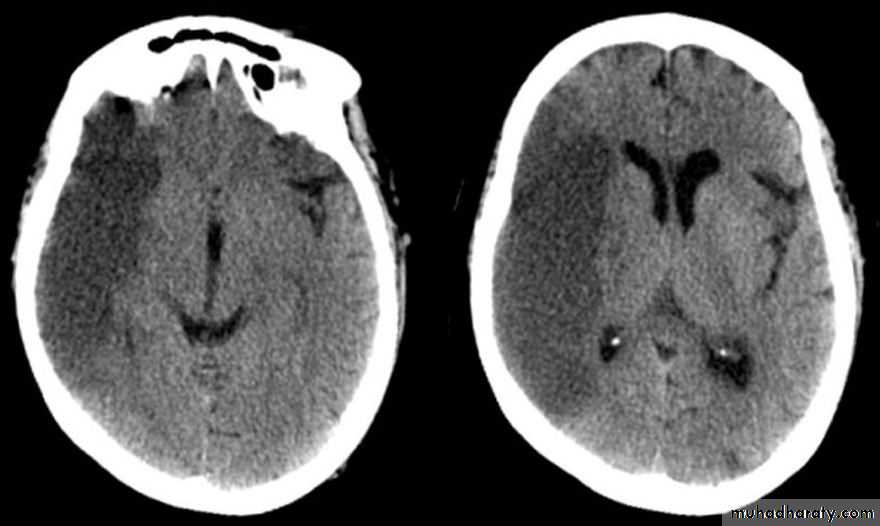

• How to identify patients with tissue at risk for guidance in selecting the appropriate therapy

• Exclude hemorrhage• Differentiate between irreversibly affected brain tissue and reversibly impaired tissue (dead tissue versus tissue at risk)

• Identify stenosis or occlusion of major extra- and intracranial arteries